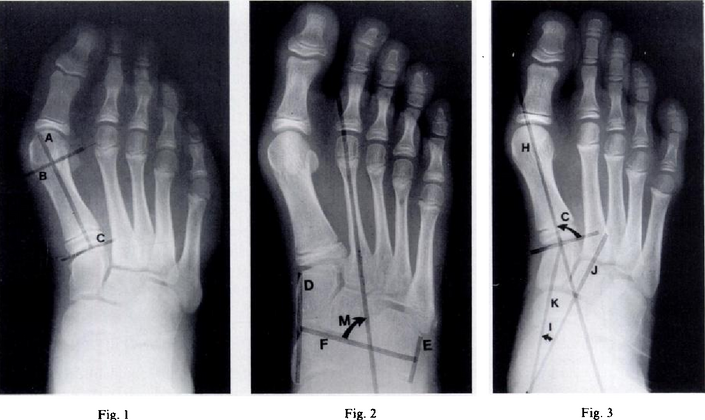

Pigeon toe can be diagnosed by physical examination alone.[10] This can classify the deformity into "flexible", when the foot can be straightened by hand, or otherwise "nonflexible".[10] Still, X-rays are often done in the case of nonflexible pigeon toe.[10] On X-ray, the severity of the condition can be measured with a "metatarsus adductus angle", which is the angle between the directions of the metatarsal bones, as compared to the lesser tarsus (the cuneiforms, the cuboid and the navicular bone).[11] Many variants of this measurement exist, but Sgarlato's angle has been found to at least have favorable correlation with other measurements.[12] Sgarlato's angle is defined as the angle between:[9][13]

• A line through the longitudinal axis of the second metatarsal bone.

• The longitudinal axis of the lesser tarsal bones. For this purpose, one line is drawn between the lateral limits of the fourth tarsometatarsal joint and the calcaneocuboid joint, and another line is drawn between the medial limits of the talonavicular joint and the 1st tarsometatarsal joint. The transverse axis is defined as going through the middle of those lines, and hence the longitudinal axis is perpendicular to this axis.

This angle is normally up to 15°, and an increased angle indicates pigeon toe.[9] Yet, it becomes more difficult to infer the locations of the joints in younger children due to incomplete ossification of the bones, especially when younger than 3–4 years.[citation needed]